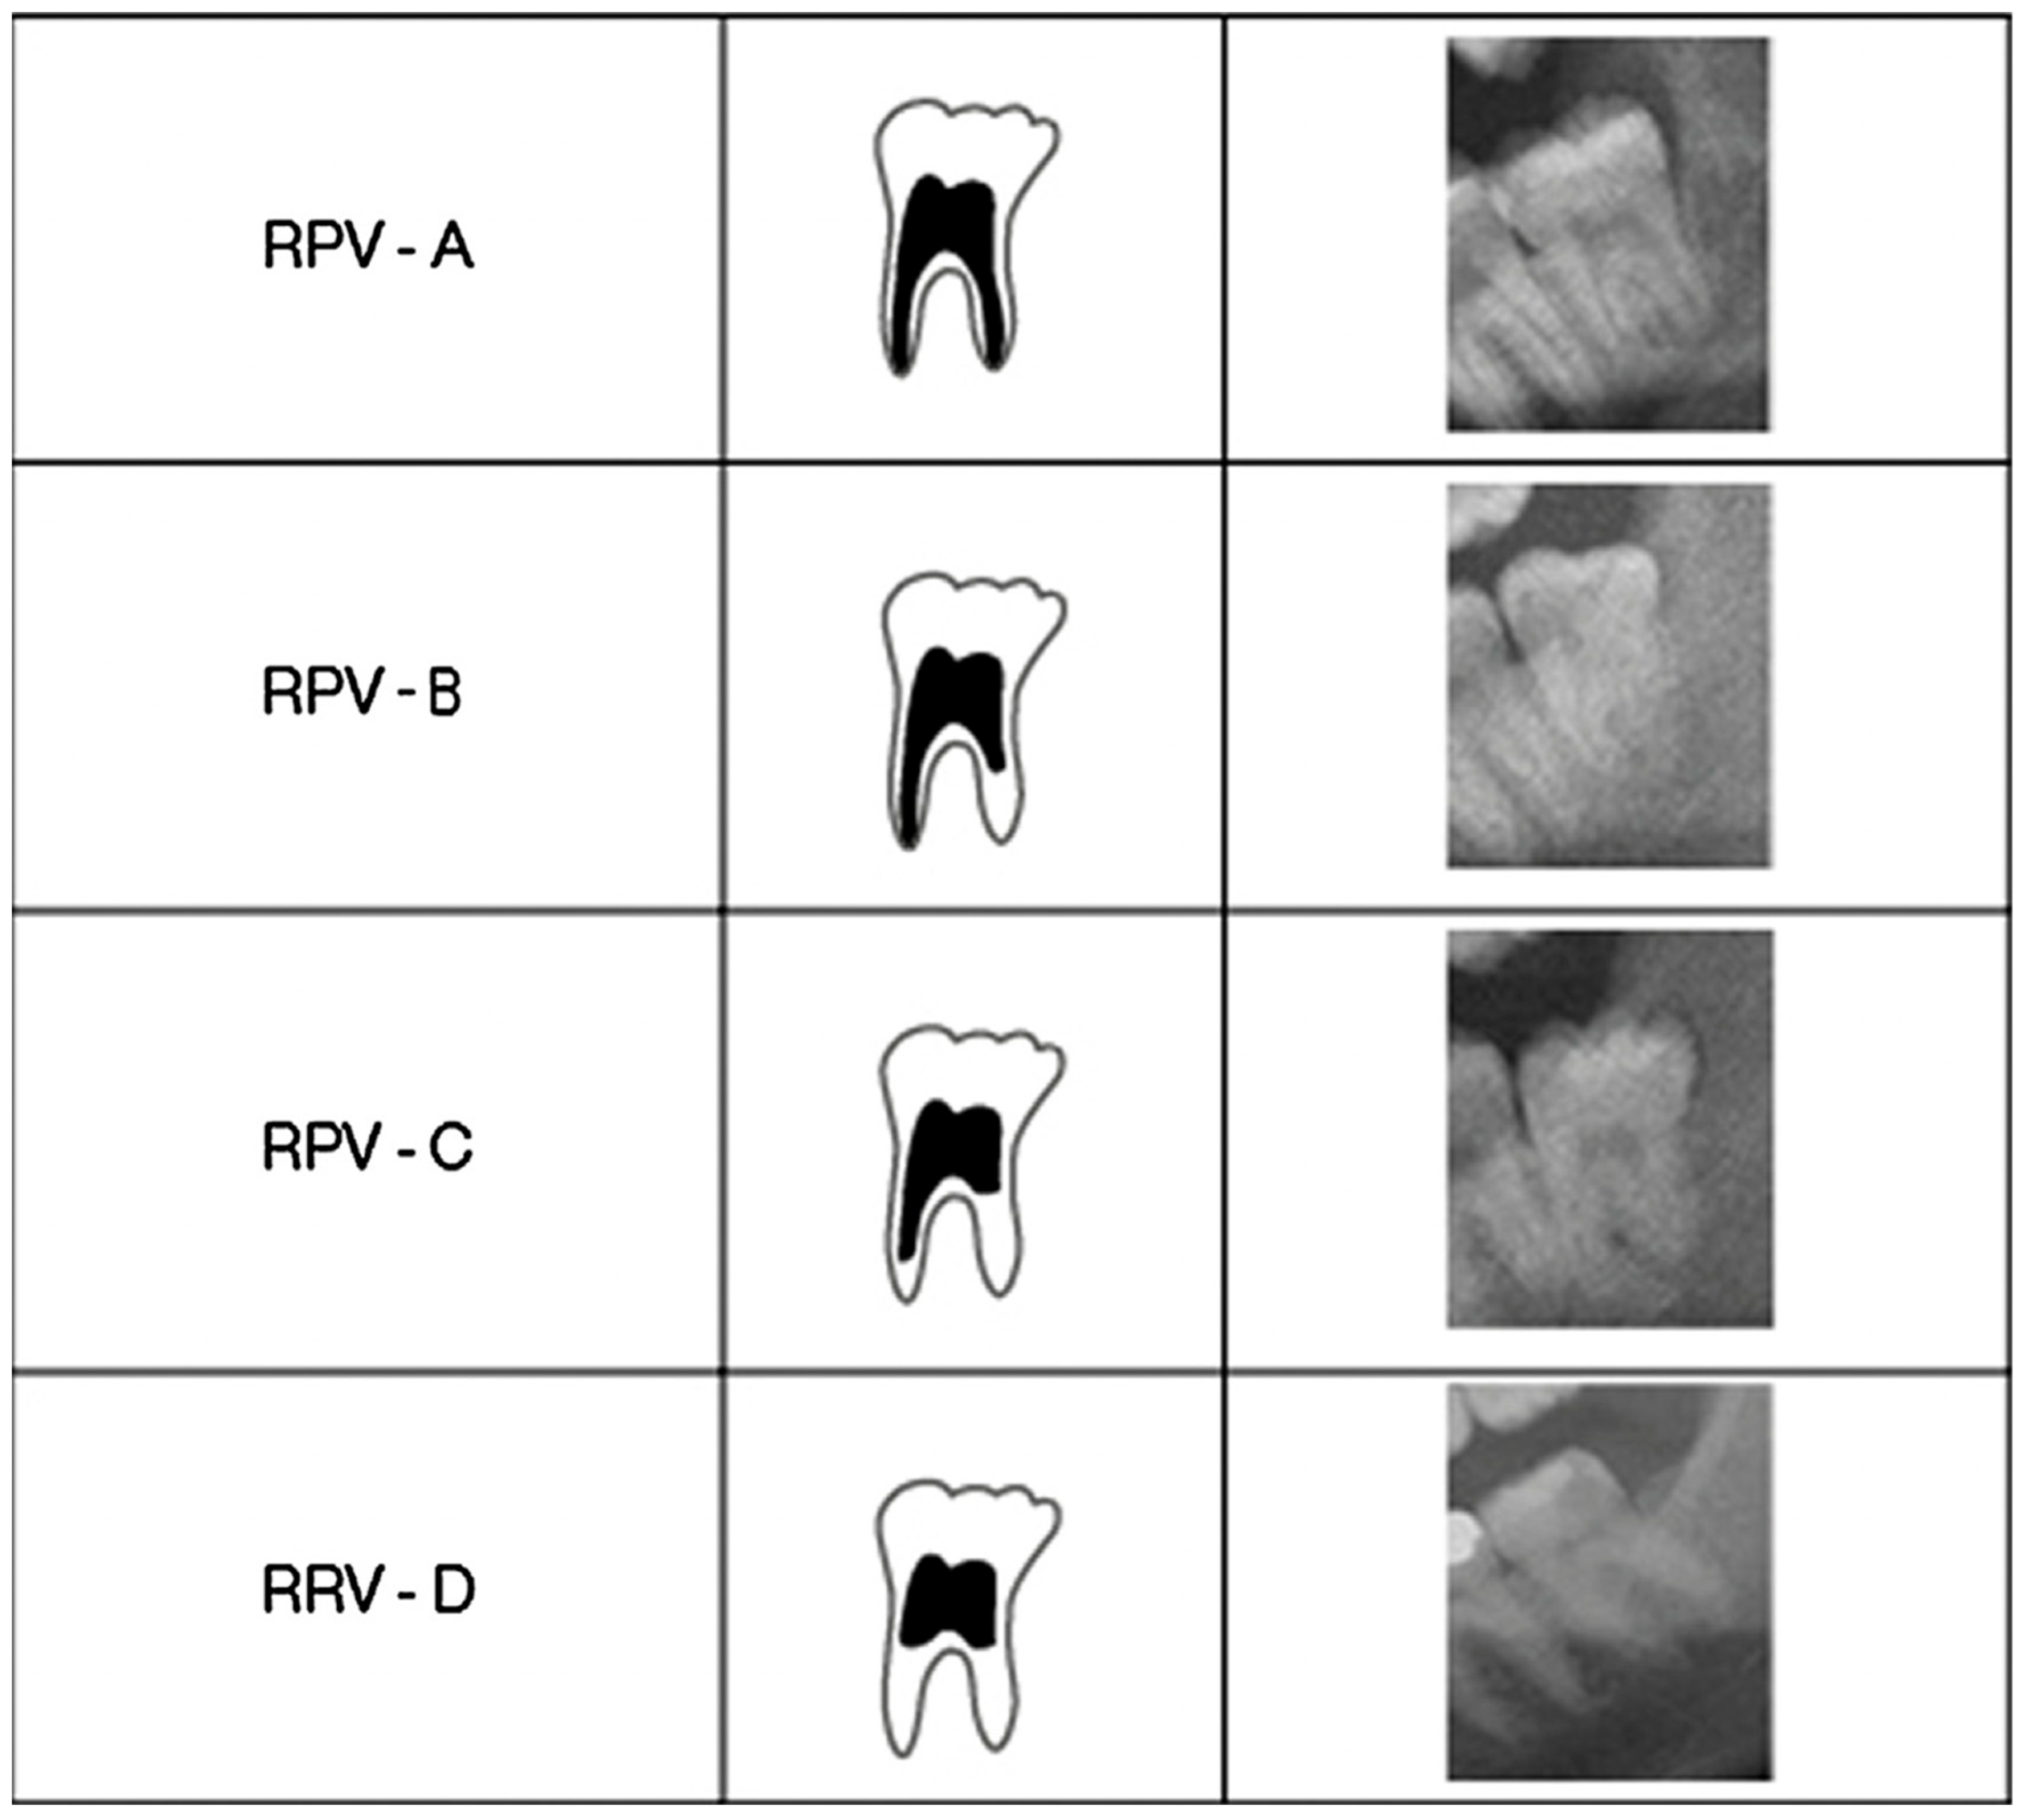

Data were manually entered into an excel spreadsheet. Each patient’s ID number, date of birth (DOB), date on which the panoramic was taken (DOR), CA (calculated or true age), PLV (Periodontal Ligament Visibility), and RPV (root pulp visibility) were recorded, respectively. Some identification information could not be found for certain radiographs based on radiographic exposure or scanning errors. Radiographs were graded based on four categories for PLV—PLV A; PLV B; PLV C; and PLV D (Figure 1)—and four categories for RPV—RPV A; RPV B; RPV C; and RPV D (Figure 2). The exact visual representations of the stages were used from Lucas et al. study [4]. Both research papers contained visual representations of what each stage would ideally look like and were, respectively, utilized as a guide to analyze and grade the panoramic images. For RPV, earlier stages show more root pulp in comparison to the later stages, which showed partial pulp coverage on the root(s); for PLV, earlier stages showed more periodontal ligament as a well-defined corticated radiolucent border around the tooth in comparison to the later stages. Statistical significance was set at p < 0.05 and an independent sample t-test was conducted to assess the average Age at Assessment of the stages in PLV and RPV between females and males.

Figure 2.

Illustration of Root Pulp Volume (Lucas et al., 2017) [4].